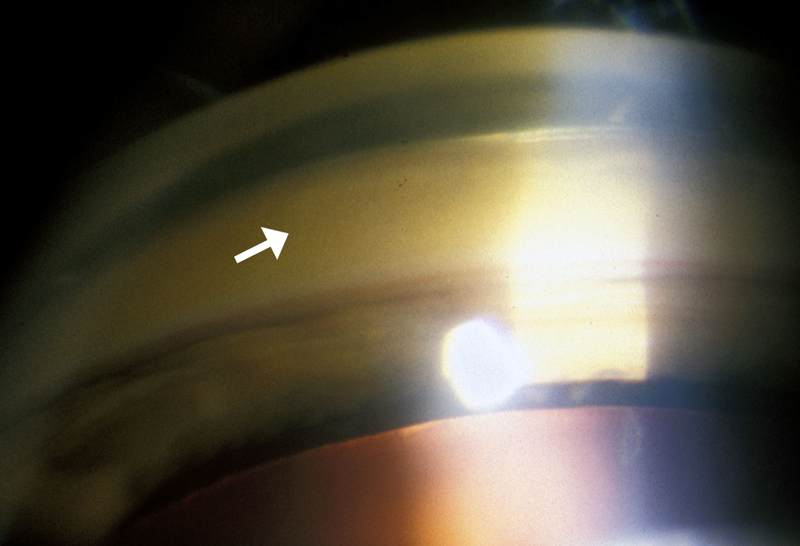

• Anterior segment see Figure 1. Scleral icterus OU, 1-2 mm golden brown band seen at the limbus OU.

Figure 1

Figure 1a: Golden Brown Kayser-Fleischer ring Figure 1b: Higher magnification photo of golden brown ring at the level of Descemet's membrane

Figure 1c: Gonioscopy of angle, showing golden brown deposit in Descemet's membrane

The presence of Kayser-Fleischer rings in combination with low serum ceruloplasmin is considered diagnostic of Wilson's disease based on Sternlieb's criteria (Martins da Costa, 1992). In the cornea, the excess circulating copper is deposited in Descemet's membrane and is usually seen as a golden brown ring located in the peripheral cornea, beginning at Schwalbe's line and extending less than 5 mm onto the cornea (see video). The ring may also appear as greenish yellow, ruby red, bright green, or ultramarine blue. It is almost always bilateral and appears superiorly first, then inferiorly, and then later becomes circumferential (Kim, 1979). In the earlier stages of disease, gonioscopy is often needed to detect this subtle finding, but in advanced disease it can be seen with the naked eye.